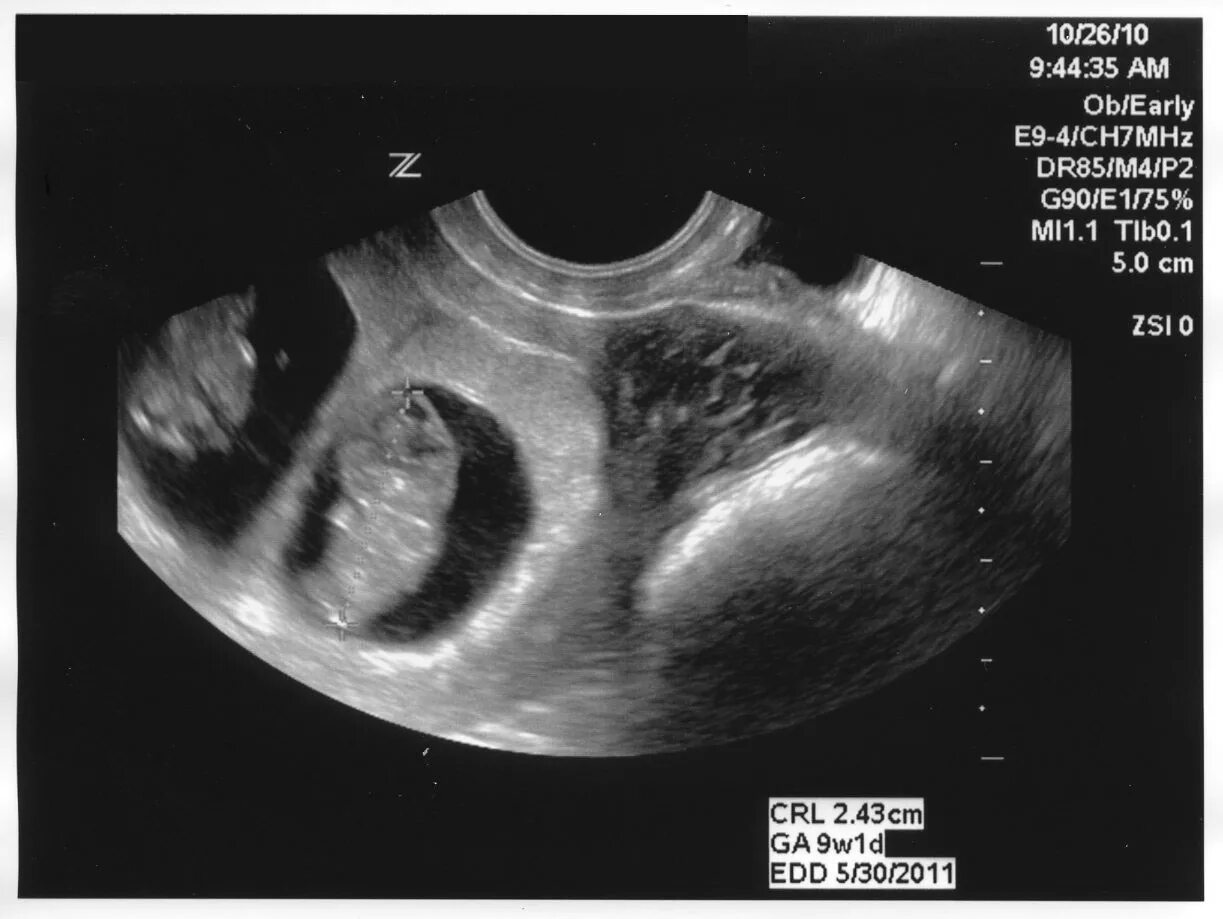

1 9 неделя беременности